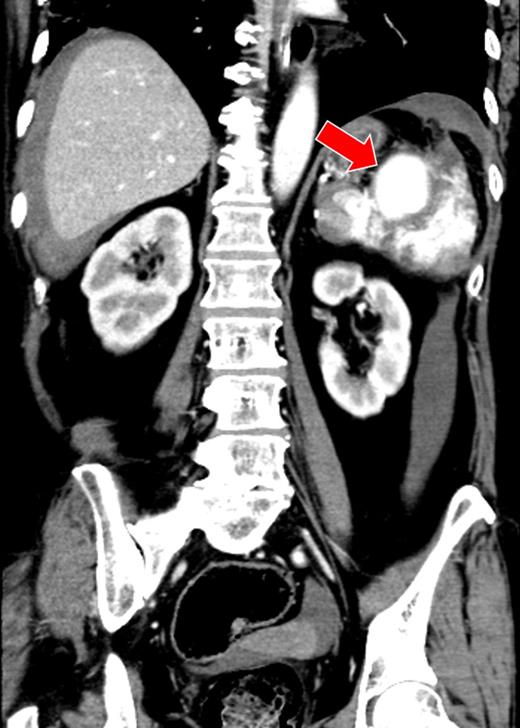

A 52-year-old woman was admitted to the emergency department with altered mental status. On admission, her mental status improved to E3V4M6 on the Glasgow Coma Scale with a BP of 95/72 mmHg and HR of 92 bpm. She was found to be anemic and coagulopathic (Hb, 9.6 g/dl; Ht, 31.0%; PT-INR, 2.68 and APTT, 38.4 s). She had a history of mitral valve replacement 3 months ago and was taking warfarin and sarpogrelate. CECT showed a giant splenic artery aneurysm, splenic laceration and hematoma (Fig. 3). A diagnosis of hemorrhagic shock secondary to ruptured splenic aneurysm was made and IR was consulted. The source of hemorrhage could not be identified because of the giant aneurysm and therefore hemorrhagic shock persisted, despite aggressive resuscitation. Localization of the hemorrhagic source was abandoned and transient occlusion of the splenic artery using a microballoon catheter was performed (arrival to occlusion, 140 min; arrival to angiography suite, 110 min and procedure time to occlusion, 17 min). The hemorrhage and patient's hemodynamics subsequently improved after a total of 4 units of RCC and 6 units of FFP being transfused. A splenectomy was performed on Day 2 after correction of the patient's coagulopathy (Ht, 27%; PT-INR, 1.02 and APTT, 33.8 s). On examination, the giant splenic aneurysm was found to be a pseudoaneurysm complicated by an abscess at the hilum of the spleen, yielding a final diagnosis of ASR due to infection. The patient was moved to the general ward on Day 3, and discharged from the hospital on Day 12.

There was a massive hematoma surrounding the spleen and the liver. A giant splenic aneurysm (40 × 50 mm) and splenic laceration are seen (arrow).